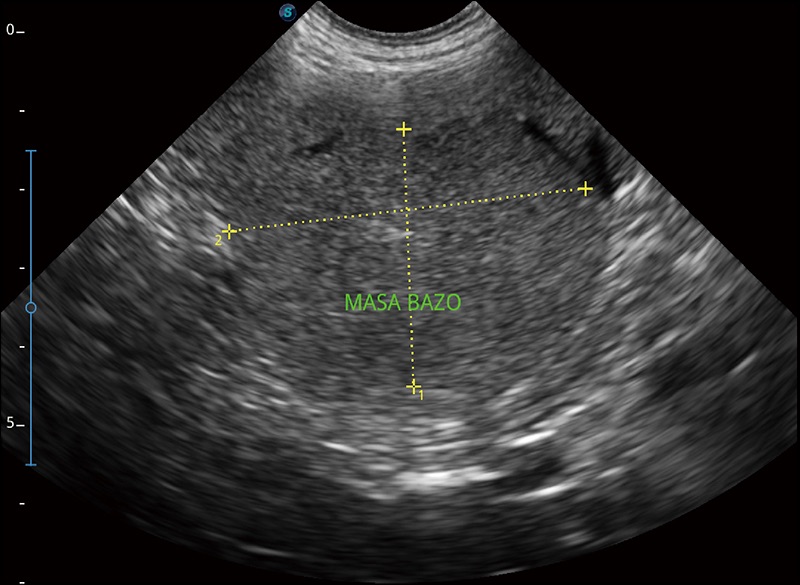

α1卓越的图像质量和便捷的工作流程,使每位宠物医生都能轻松扫查。其全面的兽用应用功能和紧凑型的结构设计,可以满足动物检查的多种需要。专业的预设检查模式和多领域测量软件包有助于为不同类型的动物提供检查, 让宠物医生能够出色的完成工作。